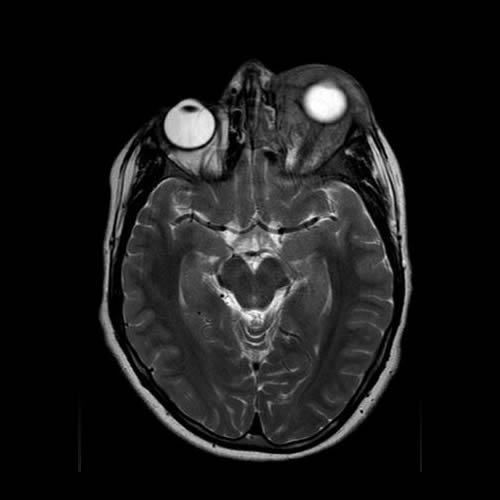

Agosto 2022. Hospital Italiano Paciente de 14 años de edad, que consulta por edema palpebral izquierdo de 15 dias de evolucion.